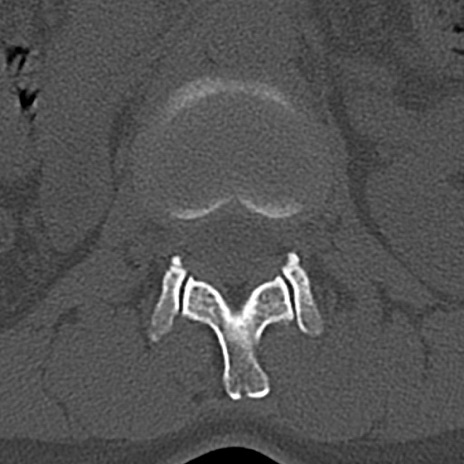

【整形】TIPS症例4 腰椎CT(横断像)

腰椎CT

横断像と矢状断像